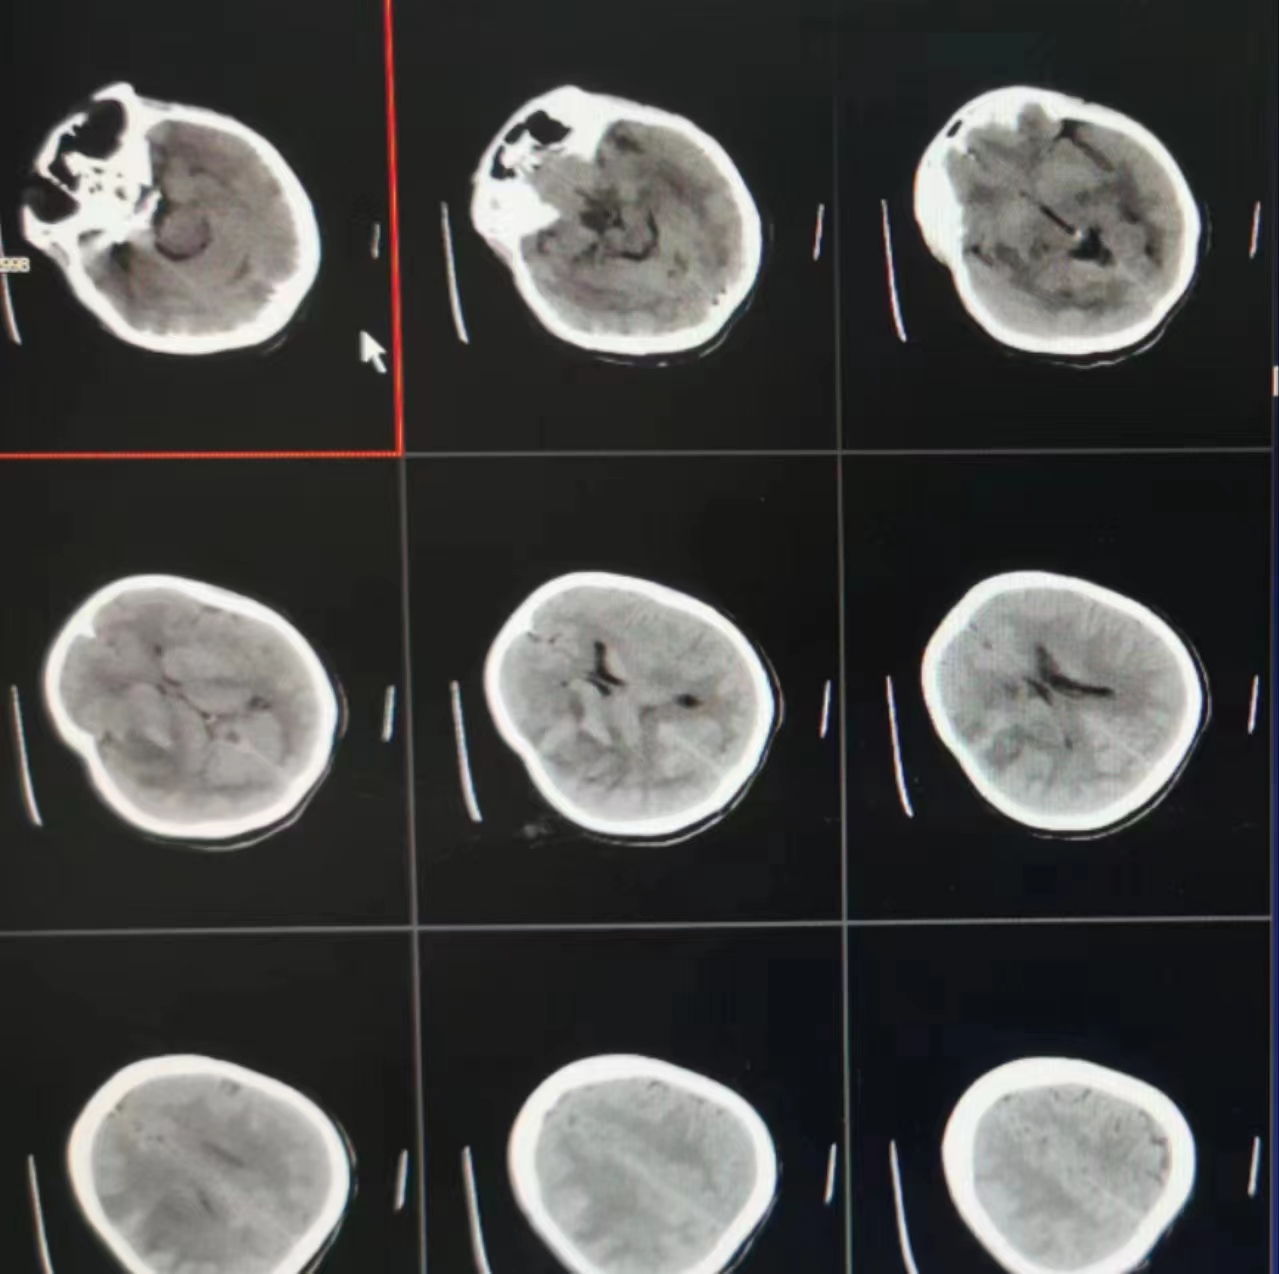

患者,女,40岁,因反复头晕耳鸣1年入院,经MRI、CTA、DSA检查后发现右侧颈内动脉海绵窦段巨大复杂动脉瘤。且为三个紧密相连瘤体,大小分别为20*21mm、20*21mm、6*8mm。病变颈内动脉段走行复杂结构不清,管壁瘤化严重,血流导向装置置入是唯一的介入治疗手段,但是由于瘤体巨大,结构复杂,其手术复杂程度犹如跳水运动员舒展双臂,向上跃起,弯腰抱住绷直的双腿在空中向前翻腾1周,右转体360度再翻腾1周完美入水,目前这样的高难度动作还没有人能够完成,但在介入手术台上任军主任团队用这样的高难度动作将导丝双腔360度成袢过中间导管,利用AB支架远端锚定解导管袢,然后释放密网支架锚定解密网支架袢。虽然手术难度大,风险高,但他们经过充分的术前讨论和精心的准备,制定了详细的手术方案和严密的应急预案,最终历经4小时的努力,成功完成手术,缓解了患者的症状。

血流导向装置是一种高金属覆盖率的密网支架,其可以通过改变血流动力学和血流方向促进动脉瘤腔内血流淤滞和血栓形成,促进支架内的内膜组织增生,达到修复病变血管作用,在治疗颅内巨大动脉瘤方面拥有其它方法无可比拟的优势,是目前国际上治疗颅内巨大复杂动脉瘤最新、最有效的技术。